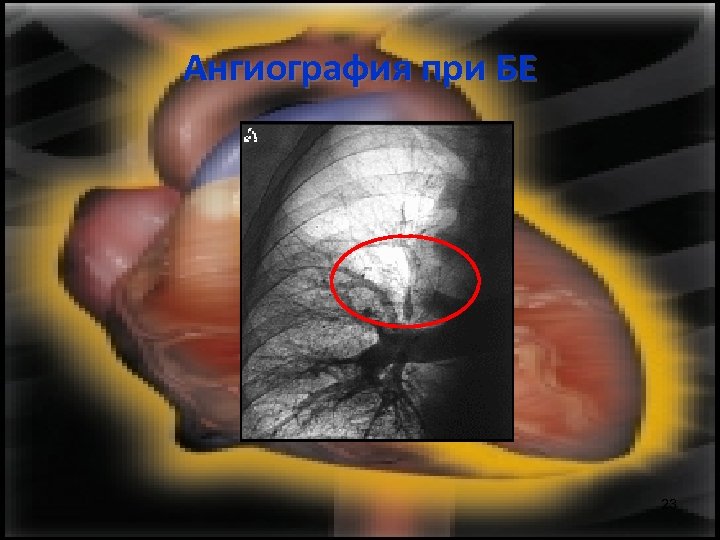

Образно изследване на гръдния кош • Белодробна ангиография: – Стандарт за доказване на БЕ – Негативната БАГ изключва диагнозата БЕ • ЯМР – чувствителност 85% и специфичност 96% за централни, лобарни или сегментарни емболи 19

Ангиография при БЕ 23